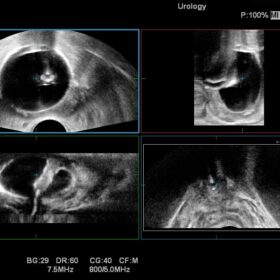

Ultrasound Noblus – Image Gallery and Videos

The Noblus offers premium modalities that can be exploited in many different clinical situations. Although compact in design, the powerful engine of the Noblus enables functions such as Real-time Tissue Elastography (RTE), dynamic Contrast Harmonic Imaging (dCHI), real-time 3D with STIC (Spatio-temporal Image Correlation) option and CW Doppler, features previously found only on larger cart-based systems.